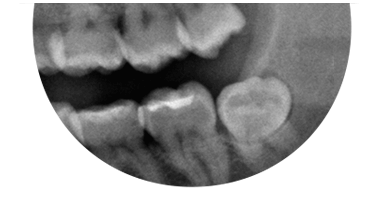

Paciente de 76 anos do sexo masculino

Plano de tratamento: Colocação de 4 implantes superiores e 2 implantes inferiores. Confeção de uma barra superior e colocação de 2 locators® na parte inferior. Confeção de uma prótese superior e outra inferior removível, com encaixes na barra e locators®.